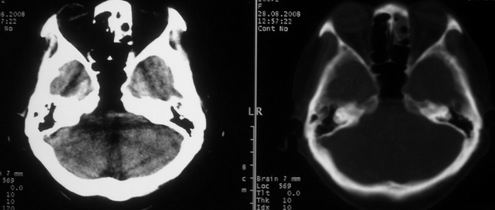

女,55岁,右侧颌下肿物3年。

右侧胸锁乳突肌后方软组织密度肿块,界限清楚。多考虑:血管源性肿瘤!

鼻咽左侧壁增厚,呈结节样突入鼻咽腔内,左侧咽隐窝消失,须考虑鼻咽癌可能,建议鼻咽纤维镜检查以明确诊断。

至于右侧颌下间隙的结节影,如果不考虑病史的话,可以诊断为淋巴结转移。但是结合病史“右侧颌下肿物3年”,又不象淋巴结转移了。建议ct增强扫描明确结节与右侧颌下腺的关系,或者穿刺活检定性。

右侧胸锁乳突肌内侧略低密度结节,应该是静内静脉而不是淋巴结。